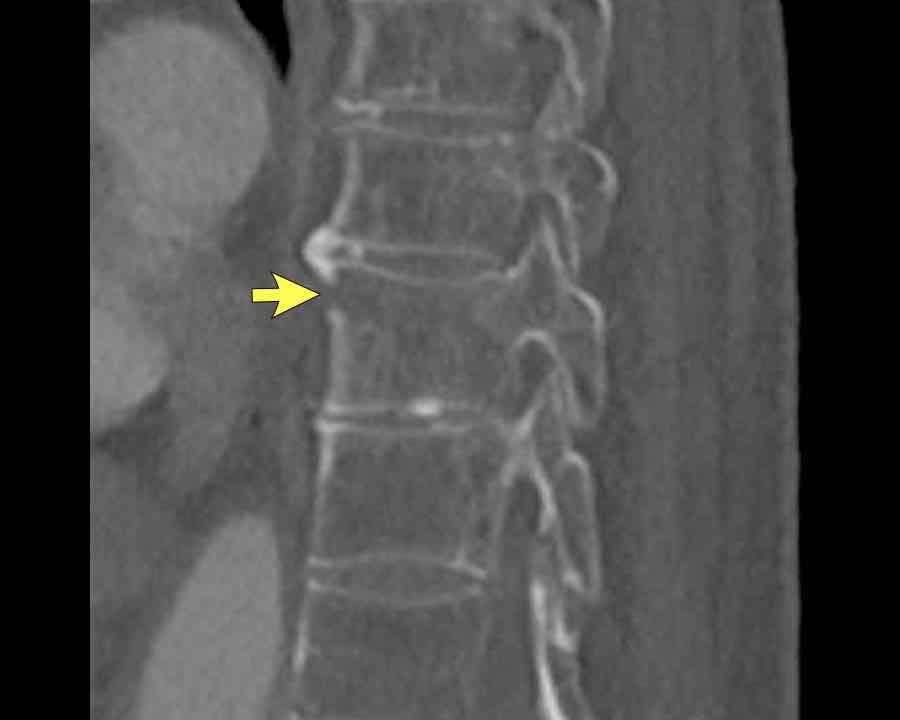

Scroll through images.

What are the findings?

Findings

- C injury? No.

- Signs of a rigid spine?

Yes, so be aware of potentially very subtle B3 injury. - A subtle fracture on the anterior vertebral body is seen (arrows).

Conclusion

Injury type B3.